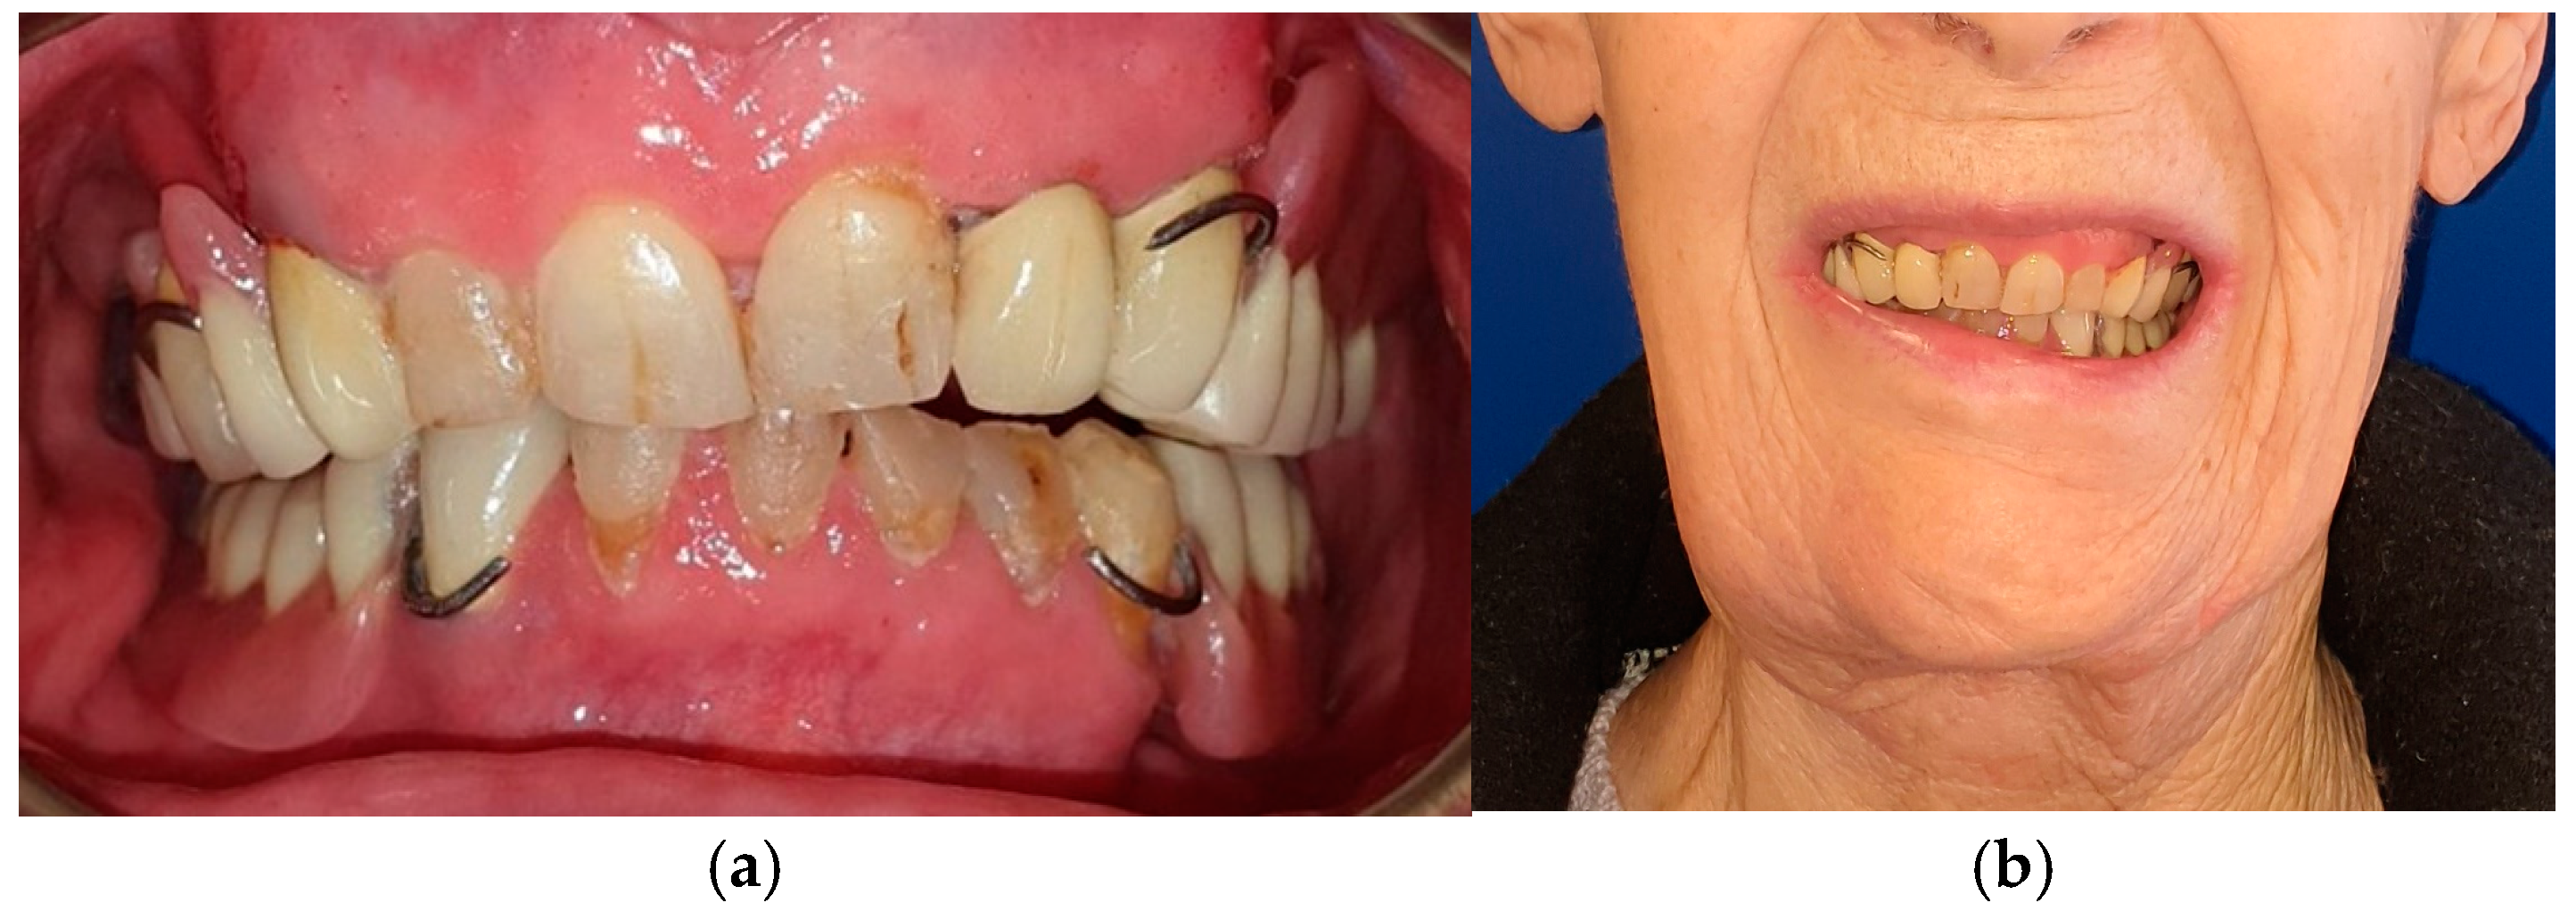

The patient in Case 1 had undergone surgery to remove a tumor that intersected the angle of the mandible. (L2) (Figure 1 and Figure 2). The upper elements were extracted soon after due to periodontal and endodontic issues. After being initially rehabilitated with a complete removable prosthesis (to regain function and aesthetic), two implants were subsequently placed in the 3.2 and 4.4 areas, and the final prosthesis was built in resin with a ball retention mechanism (Figure 3 and Figure 4).

Figure 1. Patient with hemimandibulectomy L2 in lateral (a) and front (b) extraoral view.